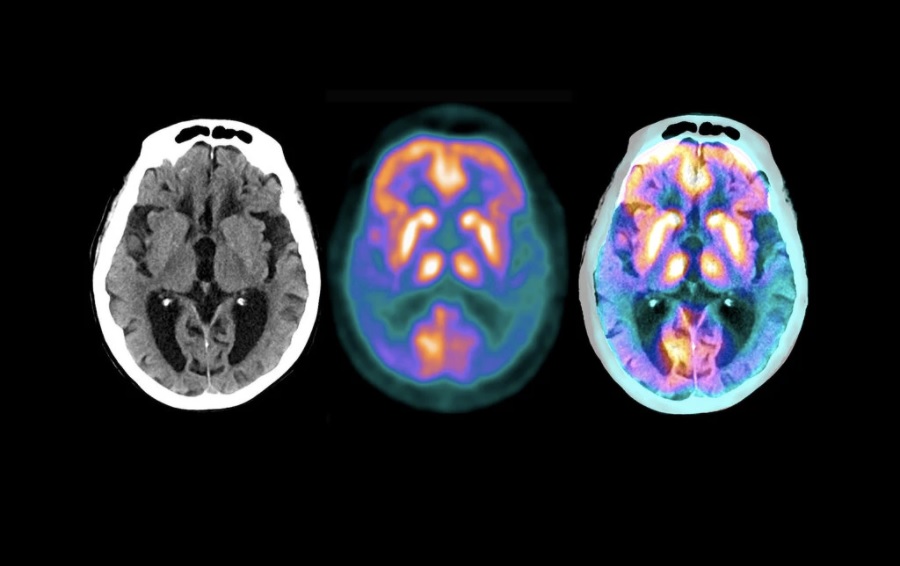

治疗老年痴呆症显一线曙光,礼来公司透露二期临床试验结果

【《华人》传媒编辑王惠豫2021年1月12日】老年痴呆症(Alzheimer,中文名:阿尔茨